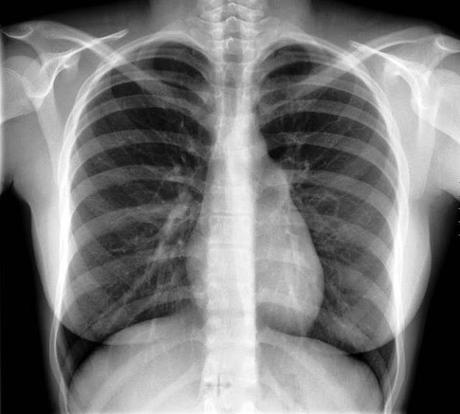

Un poco por comparar esa cuestión de tamaños, a continuación la imagen de un corazón con un tamaño normal:

Tener un corazón grande o tener grandeza de corazón, en medicina, nada tienen que ver con lo que estas cosas significarían en la calle, adónde tales expresiones suelen referirse a virtudes como la generosidad o la nobleza.